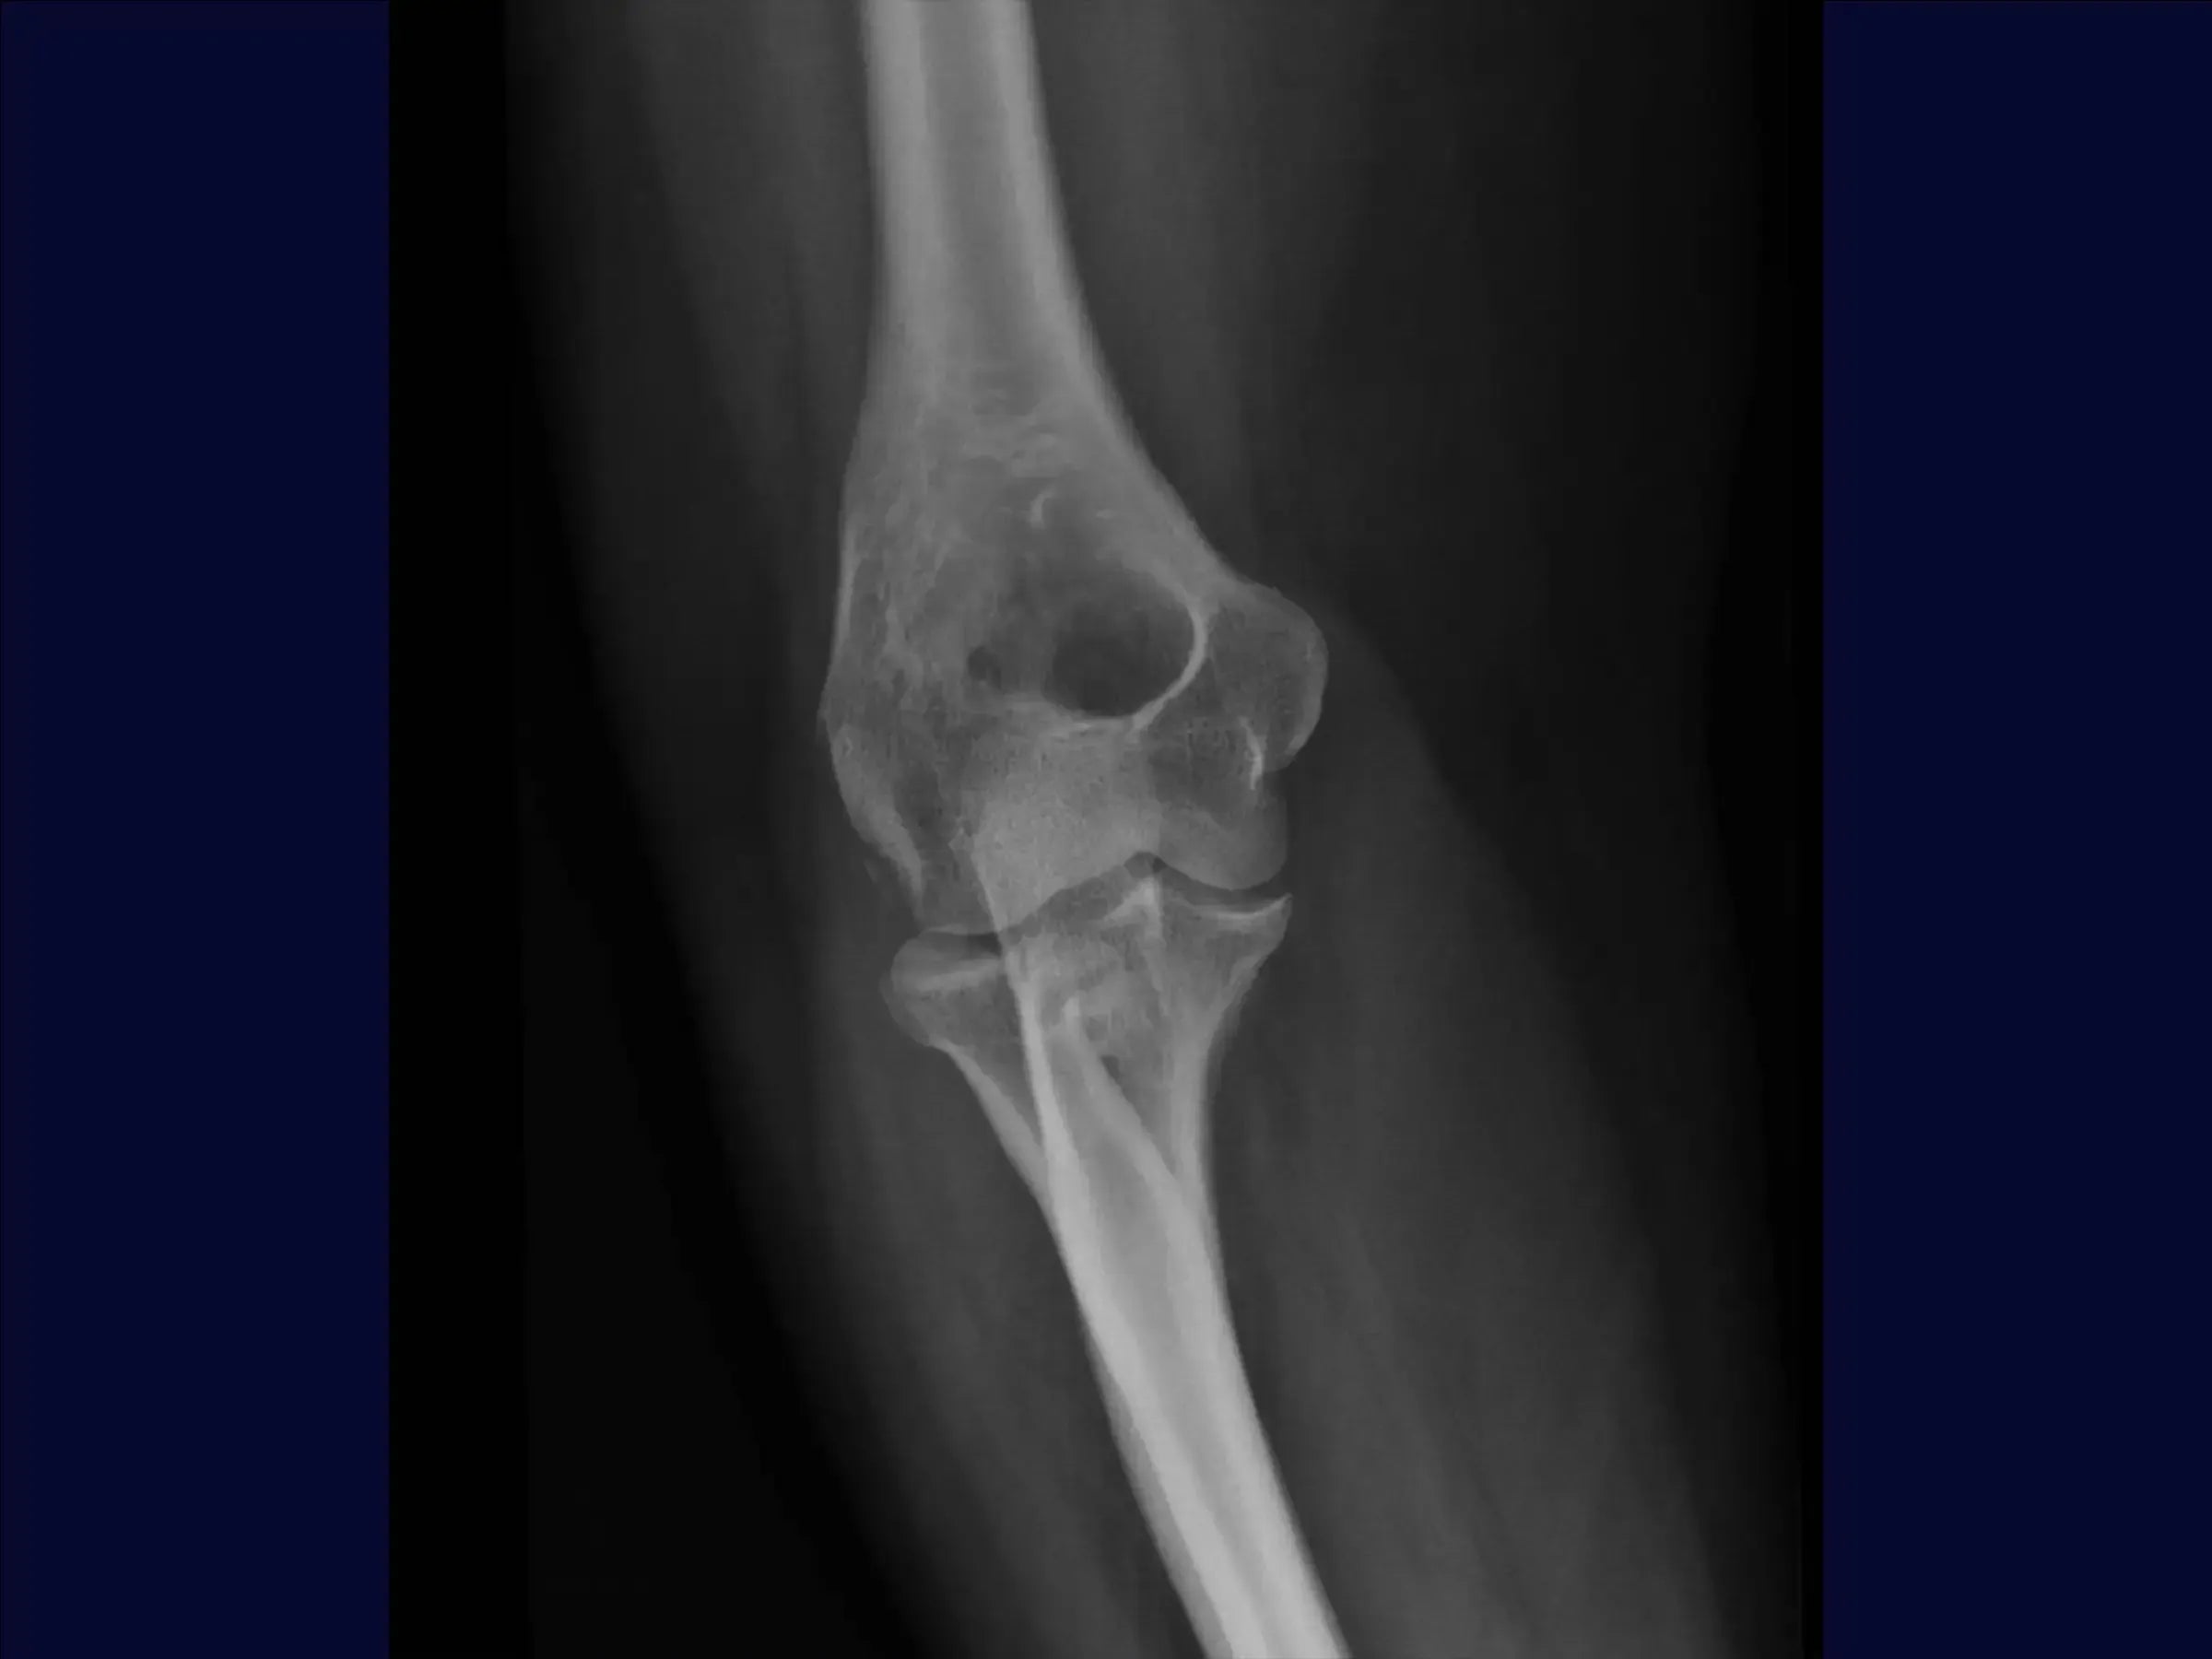

Reconstrucción de fractura multifragmentaria de cabeza radial (Mason 3) con inestabilidad asociada

Fracturas de radio (Mason 3): osteosíntesis y reparación de ligamentos para restaurar la función del codo.

Mejore sus habilidades en la reconstrucción de fracturas multifragmentarias de la cabeza radial, tipo Mason 3, asociadas con compromiso de la cápsula articular y fractura de la apófisis coronoides . Esta capacitación se centra en el abordaje quirúrgico que busca estabilizar la fractura mediante osteosíntesis , reparación integral de ligamentos y manejo posoperatorio temprano para restaurar la función del codo.

- Evaluación y planificación inicial: Interpretar radiografías para identificar fracturas complejas (Mason 3) y compromiso articular. Planificar siempre la reparación del ligamento y tener una prótesis disponible como alternativa.